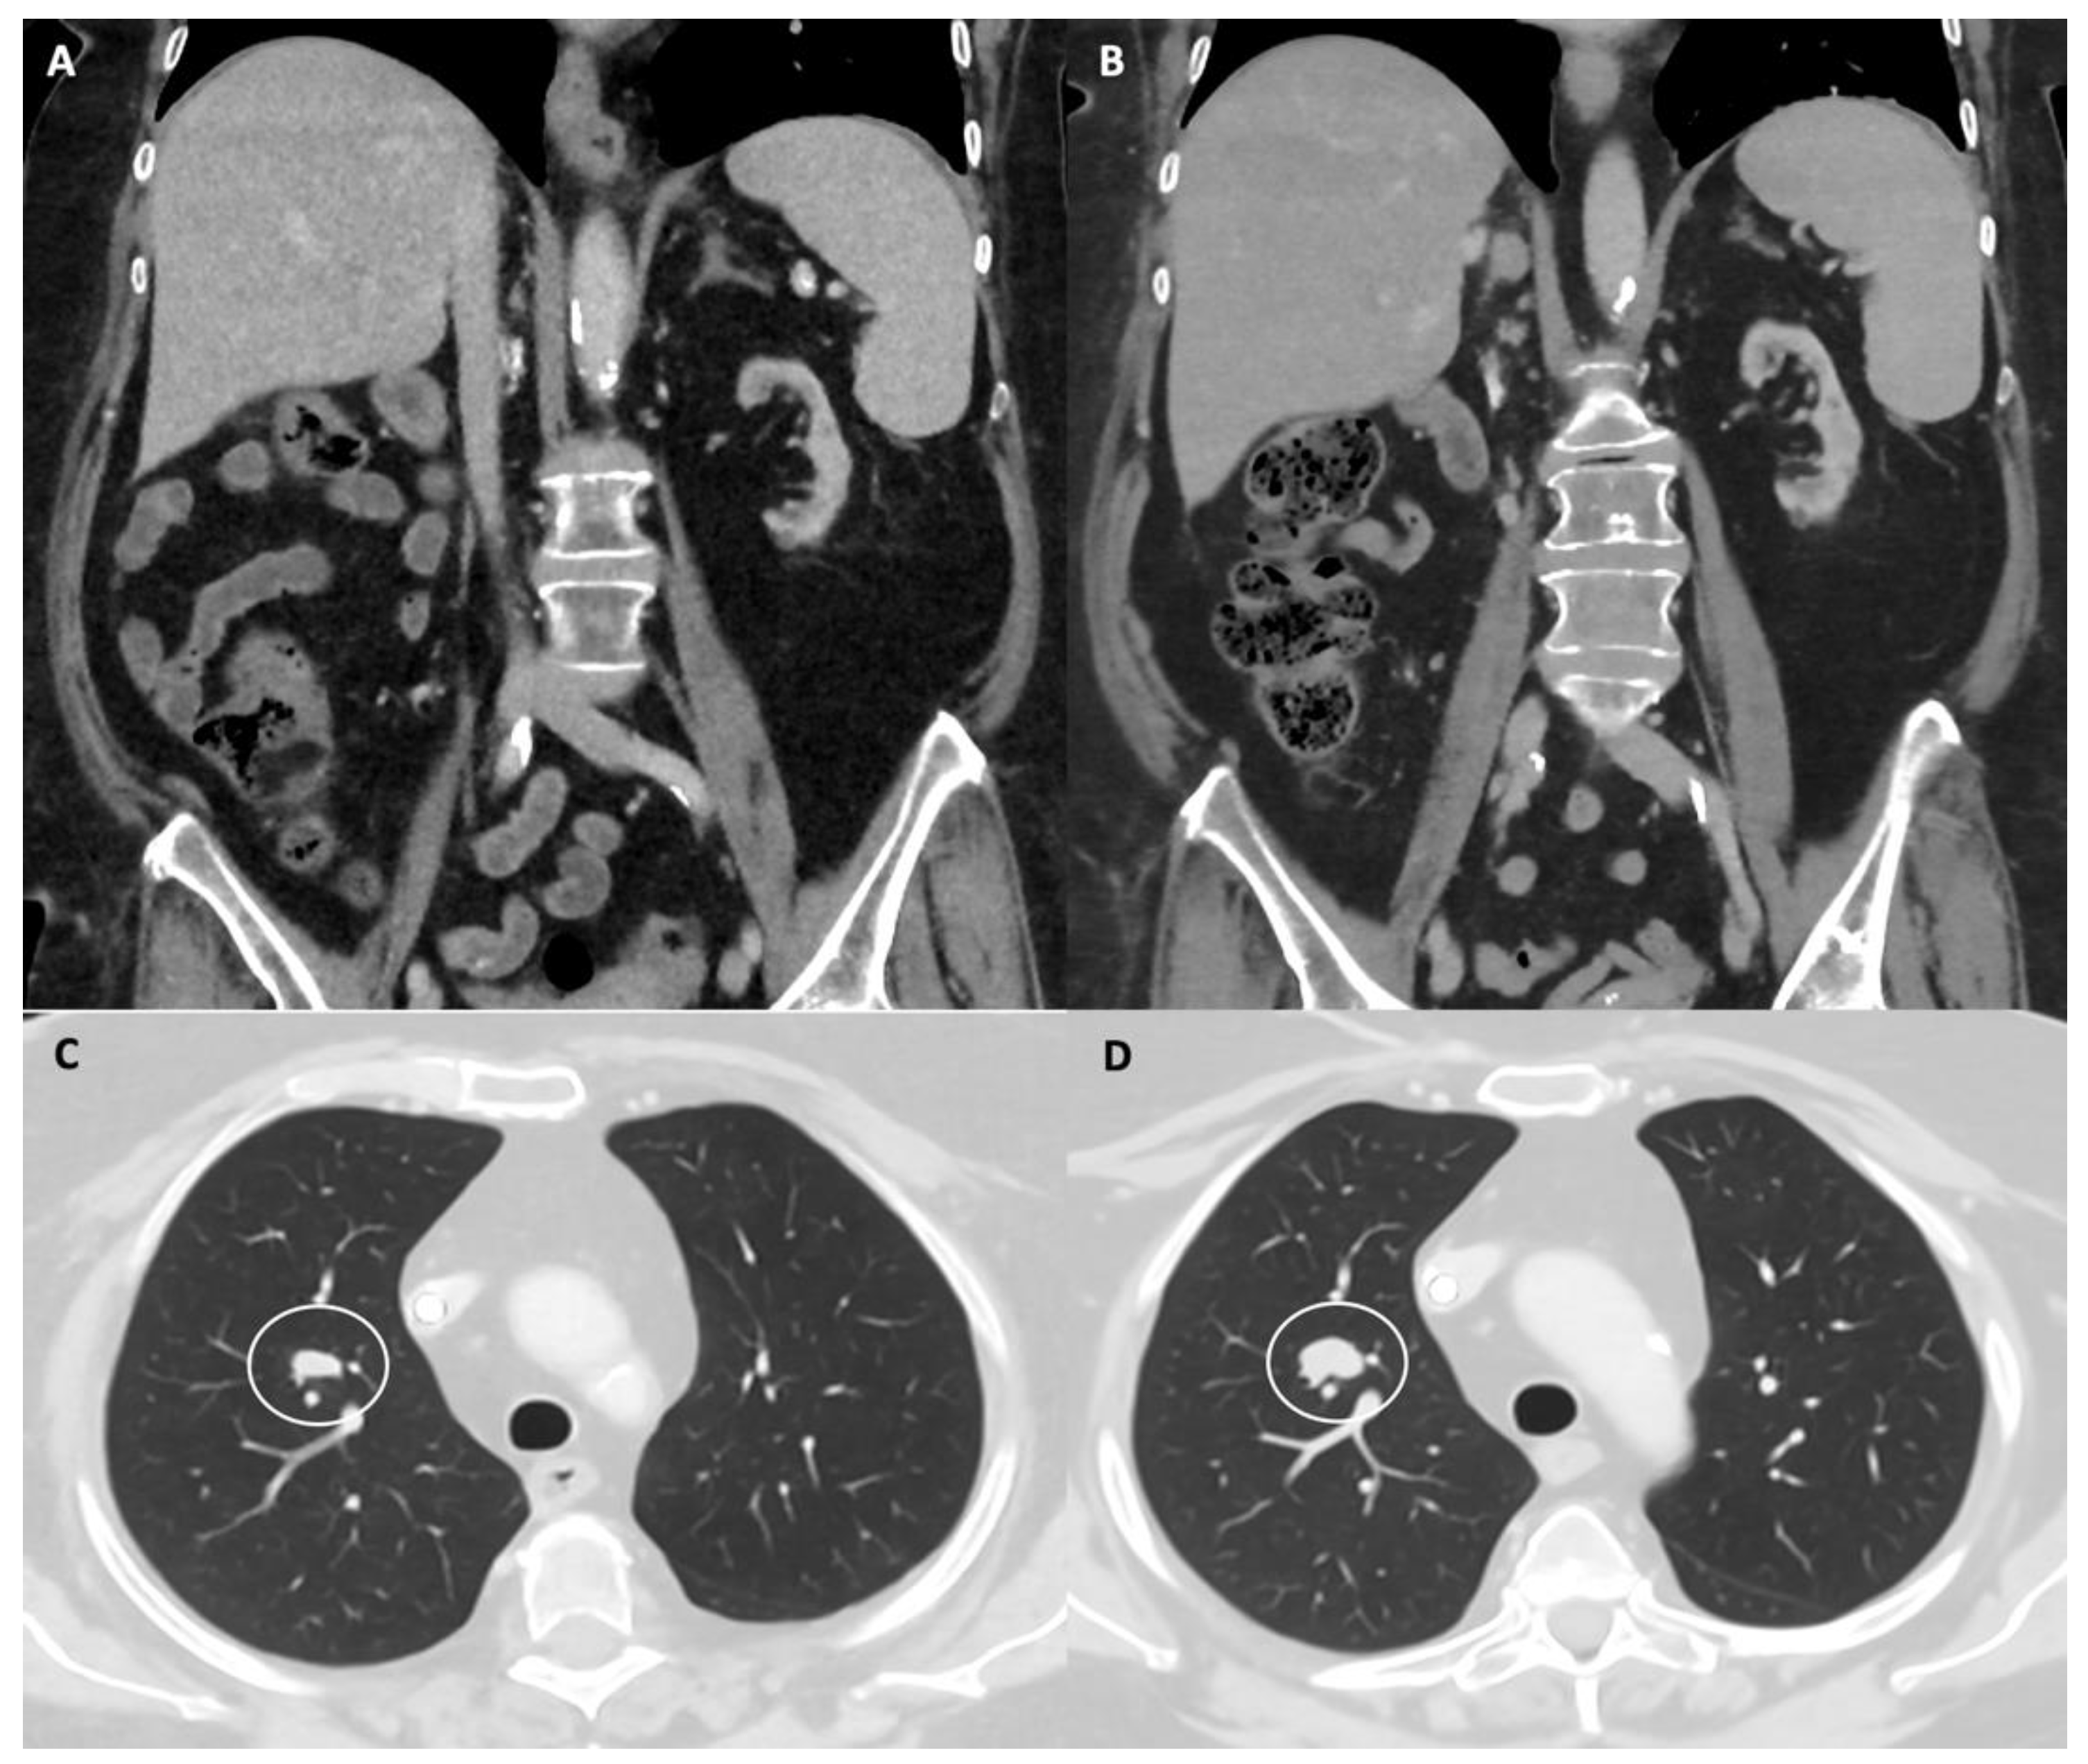

- Smith, A.D.; Lieber, M.L.; Shah, S.N. Assessing tumor response and detecting recurrence in metastatic renal cell carcinoma on targeted therapy: Importance of size and attenuation on contrast-enhanced CT. Am. J. Roentgenol. 2010, 194, 157–165. [Google Scholar] [CrossRef] [Green Version]

- Thian, Y.; Gutzeit, A.; Koh, D.-M.; Fisher, R.; Lote, H.; Larkin, J.; Sohaib, A. Revised choi imaging criteria correlate with clinical outcomes in patients with metastatic renal cell carcinoma treated with sunitinib. Radiology 2014, 273, 452–461. [Google Scholar] [CrossRef] [PubMed]

- Fujimoto, D.; Yoshioka, H.; Kataoka, Y.; Morimoto, T.; Hata, T.; Kim, Y.H.; Tomii, K.; Ishida, T.; Hirabayashi, M.; Hara, S.; et al. Pseudoprogression in previously treated patients with non–small cell lung cancer who received nivolumab monotherapy. J. Thorac. Oncol. 2019, 14, 468–474. [Google Scholar] [CrossRef] [Green Version]

- Seymour, P.L.; Cancer, C.; Group, T.; Bogaerts, J.; Perrone, A.; Medicine, T.; Ford, R.; Trials, C.; Consulting, I.; Mead, B.; et al. iRECIST: Guidelines for response criteria for use in trials testing immunotherapeutics. Lancet Oncol. 2017, 18, e143–e152. [Google Scholar] [CrossRef] [Green Version]